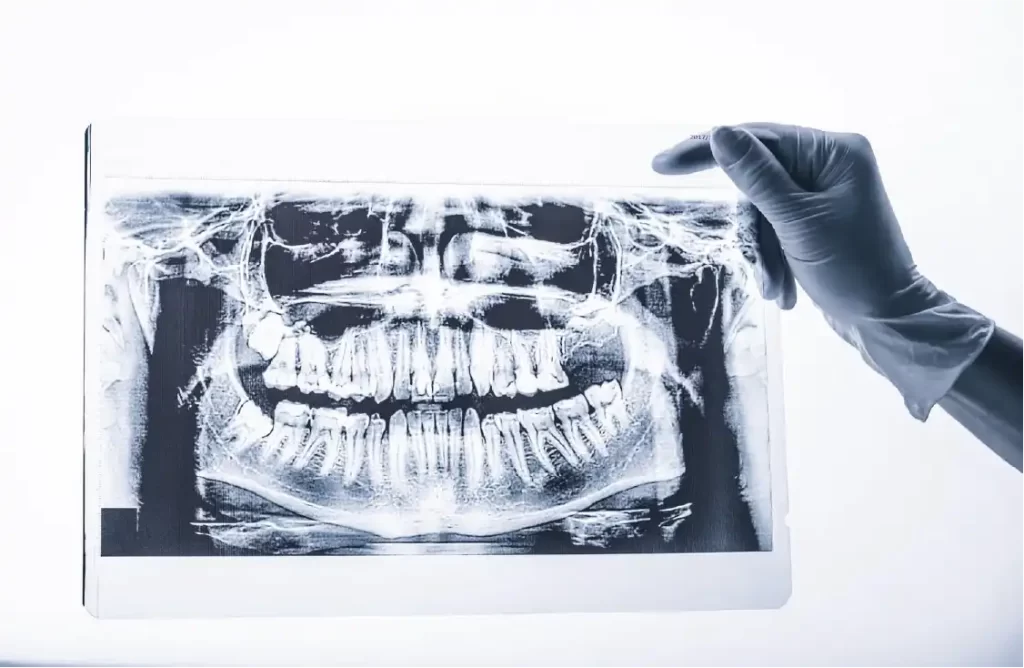

Oral Cavity Cancer

Oral Cavity Cancer Treatment

Oral cavity cancer affects tissues inside the mouth, including the tongue, gums, inner cheeks, lips, floor of the mouth, and hard palate. Squamous cell carcinoma accounts for approximately 90% of oral cavity cancers, developing from the thin, flat cells lining the mouth. These cancers can spread to nearby lymph nodes and other body parts if not detected early. Common symptoms include persistent mouth sores, white or red patches, unexplained bleeding, loose teeth, difficulty swallowing, and changes in speech. Risk factors encompass tobacco use in any form, excessive alcohol consumption, human papillomavirus (HPV) infection, sun exposure to lips, poor oral hygiene, and certain genetic conditions. Early detection significantly improves treatment outcomes, making regular dental examinations and prompt evaluation of concerning symptoms essential for optimal patient care and recovery success.

Diagnosis involves thorough clinical examination, tissue biopsy for definitive diagnosis, and imaging studies including CT, MRI, or PET scans for staging. Our team uses advanced diagnostic techniques to determine the exact location, size, and extent of cancer spread.